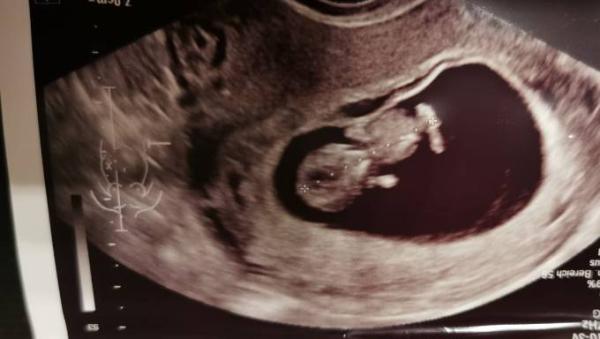

Hallo, ich war heute mit meinem Freund zum Ultraschall und nun grübeln wir zu Hause was man alles erkennt und wie das Bild überhaupt aufgenommen wurde, von oben, von der Seite, von unten. Also es wurde kein Untraschall von außen gemacht mit einem Gerät auf dem Bauch sondern von innen. Würde mich freuen über gute Interpretationen, vllt ja auch eine Hebamme oder ein Frauenarzt unter euch der mir das genau sagen könnte. Hier das Bild und noch 2 andere Bilder wie wir es interpretieren. Wir dachten jetzt das es von oben ist, quasi auf den Bauch von dem Baby raufguckt, auf die Vorderseite eventuell. Schönen Abend, danke & Lg.

Bild zu 11.SSW Ultraschallbild - Forum für Oktober - Mamis

He, ich könnte mir vorstellen, dass des was ihr als rechtes beim eingezeichnet habt vielleicht eher die Nabelschnur ist. Weil ich glaub die Beine und Arme noch nicht so groß sind... Sieht aber auf frontale Sicht aus... Da sieht das Baby eher aus wie n Gummibärchen...